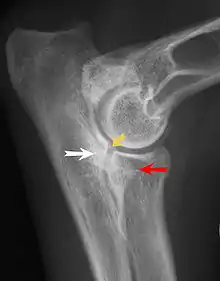

Most primary lesions are related to osteochondrosis, a disease of the joint cartilage, and osteochondritis dissecans (OCD), the separation of a flap of cartilage on the joint surface. Other common causes of elbow dysplasia include an ununited anconeal process (UAP) and fragmented or ununited medial coronoid process (FCP or FMCP).[1]

UAP is caused by a separation from the ulna of the ossification center of the anconeal process.[7] FMCP is caused by a failure of the coronoid process to unite with the ulna.

Diagnosis is through x-rays, arthroscopy or CT (computed tomography). In cases with significant lameness, surgery is the best option, especially with UAP. However, conservative treatment is often enough for cases of FMCP and OCD of the medial humeral epicondyle. The dogs are exercised regularly and given pain medication, and between the ages of 12 to 18 months the lameness will often improve or disappear.[4] Control of body weight is important in all cases of elbow dysplasia, and prevention of quick growth spurts in puppies may help to prevent the disease.